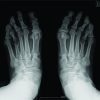

A 21-year-old female patient complained of deformity of both feet since her childhood associated with pain. The patient had undergone conservative modalities, such as orthotics, medical treatments, and insoles. The patient took physiotherapy with lifestyle modifications but had no pain relief. The patient felt that her feet were esthetically unpleasing (Fig. 1a and b). The patient was clinically evaluated and had shortening of bilateral fourth toes (Fig. 1a and b), tenderness over the bilateral fourth metatarsal ray, cock-up deformity over bilateral fourth toes, and sulcus sign over the plantar aspect of bilateral fourth toes. The patient had no comorbidities. The patient was evaluated for any associated syndromes and found to be negative. Pre-operative blood investigations and anesthesia fitness for surgery were obtained. A pre-operative plan was made using a bilateral foot X-ray. Anteroposterior and oblique views showed a 2-cm shortening in both fourth metatarsals (Fig. 2a, b) and a 5-mm shortening of the bilateral proximal phalanx (Fig. 2a, b) and malalignment of the Lelièvre parabolic arch[10] (Fig. 2c). A diagnosis of congenital bilateral brachymetatarsia of the fourth metatarsal was made. The patient was planned for lengthening of bilateral metatarsals using distraction osteogenesis with an external rail fixator[11,12].